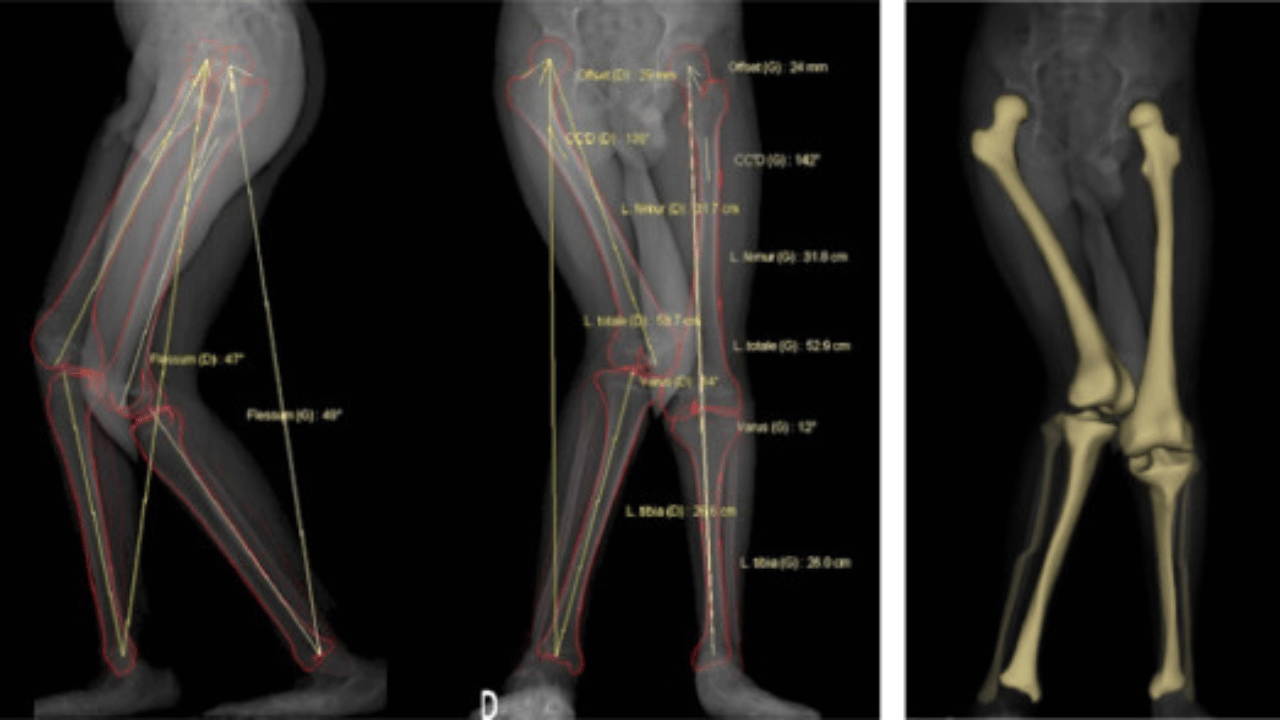

In cerebral palsy, we often observe that the two-bone systems of the limbs (the radius/ulna in the arm, and the tibia/fibula in the leg) frequently lose their articulation. Instead of working as a shifting mechanism, they behave like a single-bone unit.

That’s why, early on, you can often see CP in the radius/ulna or tibia/fibula, because they stop articulating and instead act as one unit.